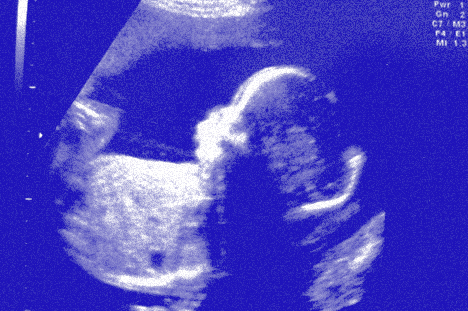

Tout en saluant ces avancées, les sages-femmes regrettent néanmoins qu’elles aient entraîné dans leur sillage une «forte médicalisation de l’obstétrique», ainsi qu’un nombre de césariennes élevé en comparaison internationale (environ un accouchement sur trois est concerné en Suisse, ndlr). «Le suivi de grossesse est ponctué de nombreux contrôles et tests, commente Heike Emery. Dans l’attente du résultat, les femmes enceintes se retrouvent dans un état d’incertitude qui peut diminuer la confiance en leur propre corps, alors que la majorité d’entre elles sont en bonne santé.»

Une notion sur laquelle se rejoignent aussi bien la sage-femme et l’obstétricien que le sociologue, c’est celle que les futurs parents évoluent dans un contexte de volonté de contrôle accrue. A l’heure où mettre au monde son premier (et parfois seul) enfant après ses 40 ans ne fait plus figure d’exception, ce constat n’étonne pas. Elle est bien loin, l’époque où les couples considéraient comme normal de perdre un, voire deux fœtus.

Professeure à la Haute école de Santé Genève — HEdS-GE, Marie-Julia Guittier constate elle aussi que le besoin de contrôle des parents est globalement à la hausse. Certes, «il faut faire attention de ne pas généraliser ce phénomène, car il dépend de la personnalité des parents et de leur culture». Reste que de nombreuses pratiques, telles que l’établissement d’un plan de naissance — «très à la mode à l’heure actuelle» –, vont dans ce sens.